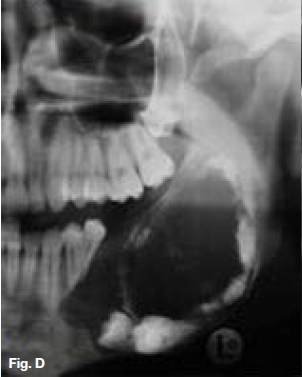

A 30-year old female presented with a swelling extending between 35 and 43, which had grown over the past ten months (Figs.A,B,C), with intermittent pain. Figures D,E,F show a similar case in a 15 year old male patient. Describe the radiological features and list your differential diagnosis.

The cropped pantomograph (Fig.B) shows a multilocular radiolucency of an expansive tumour containing varying calcifications. Figures D&E show a well demarcated multilocular lesion in the body/ramus region of the left mandible, with two displaced molar teeth, resorption of the roots of 34 and 35 and tooth-like calcifications at the borders of the lesion. The coronal T2 MRI image (Fig.F) shows a multilocular hyper-intense lesion, with no discernible calcifications. Diagnosis: the rare tumour, odonto-ameloblastoma (OA), first reported by Kemper and Root (1944). Shafer ef al (1983) described this as an odontogenic neoplasm of mixed tissue origin, consistent with both ameloblastoma and odontoma. Histologically, a typical ameloblastoma component whilst the odontoma element may be either compound or complex. Shafer et al (1983) emphasized that this is one neoplastic process with relatively highly undifferentiated tissues. Occurring most commonly in the second decade of life, it may vary in size. Smaller lesions occur between the teeth, confined to the alveolar bone between the crest of the ridge and the teeth apices (Figs. A,B&C). Buccal expansion of the cortex is common, even for smaller lesions. The odontoma component presents various stages of development, early lesions being radiolucent with radiopaque flecks. More mature lesions are better developed odontoma, resembling teeth or as a nonspecific complex odontoma mass. Importantly, this is an aggressive tumour, treated precisely as an ameloblastoma. The differential diagnosis should include: ameloblastic fibro-odontoma, Pinborg tumour, calcifying odontogenic cyst and adenomatoid odontogenic tumour.